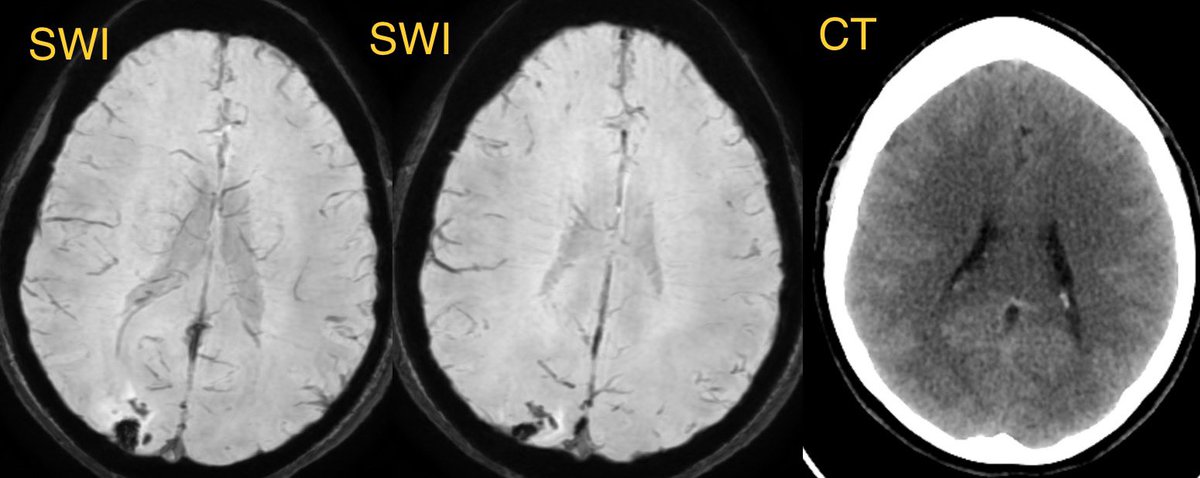

▶️convexity SAH, lobar hemorrhage, edema, and infarcts

💡 PRES also has a lot of overlap with RCVS and they can be associated with each other

PRES usually has more edema, more often bilateral, and less often has restricted diffusion and hemorrhage (though it can)